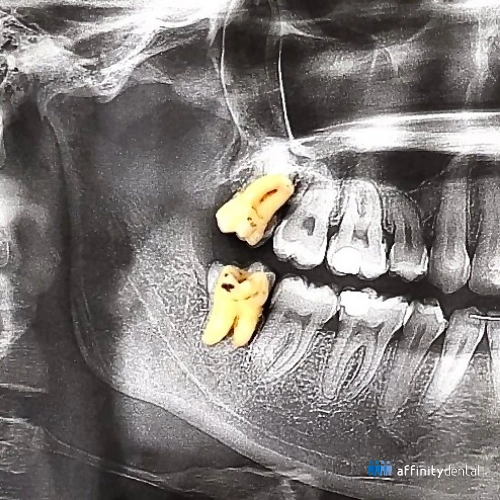

Panoramic X-ray with extracted wisdom teeth placed over the image after surgical removal at Affinity Dental Clinics Ortigas

Wisdom teeth extraction at Affinity Dental Clinics Ortigas. The X-ray shows the patient’s dentition with the removed wisdom teeth placed over the image.